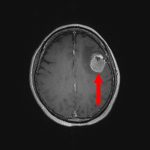

断層撮影

手術前1

手術前2